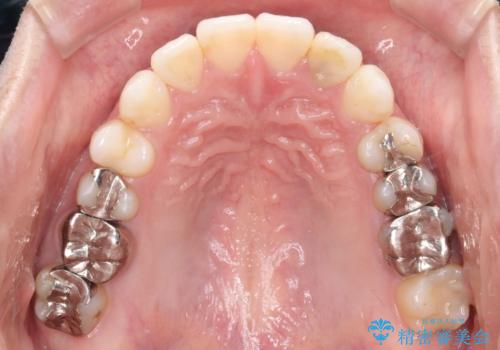

インビザラインで目立たない矯正 ガタガタの歯並びをきれいな歯並びへ

歯と歯のあいだをわずかに削りスペースを作り、ガタガタを改善する計画としました。

装着時間をしっかり守っていただけたのでスムーズに治療をすすめることができました。